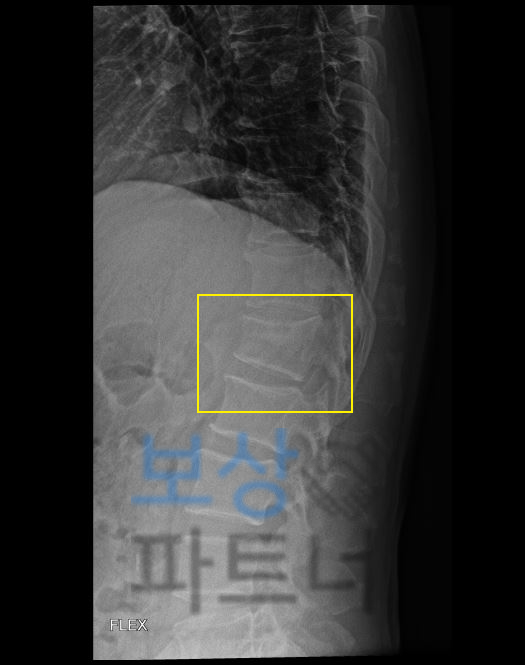

흔히 척추 1번 이라고 생각하시는 요추의 1번 골절 진단 받으셨습니다. 특히 요추1번 부위는 척추 골절 시 가장 빈번하게 발생하는 부위 중 하나인데요, 본래 자연스러운 S만곡을 형성하는 척추의 흉추와 요추가 교차하는 부위로서 추락사고, 낙상사고, 미끄러짐 사고에 금이가고 골절되는 사고가 많이 일어납니다.

요추1번 골절된 김@@님은 다행히 골밀도도 나쁘지 않아 보존적 치료로 TLSO 보조기 착용하며 3개월 정도 침상안정을 취하셔야 했는데요, 이러한 상황에 내가 가입해둔 보험에서 내가 가입한 보험에서 후유장해 항목 찾아보세요!